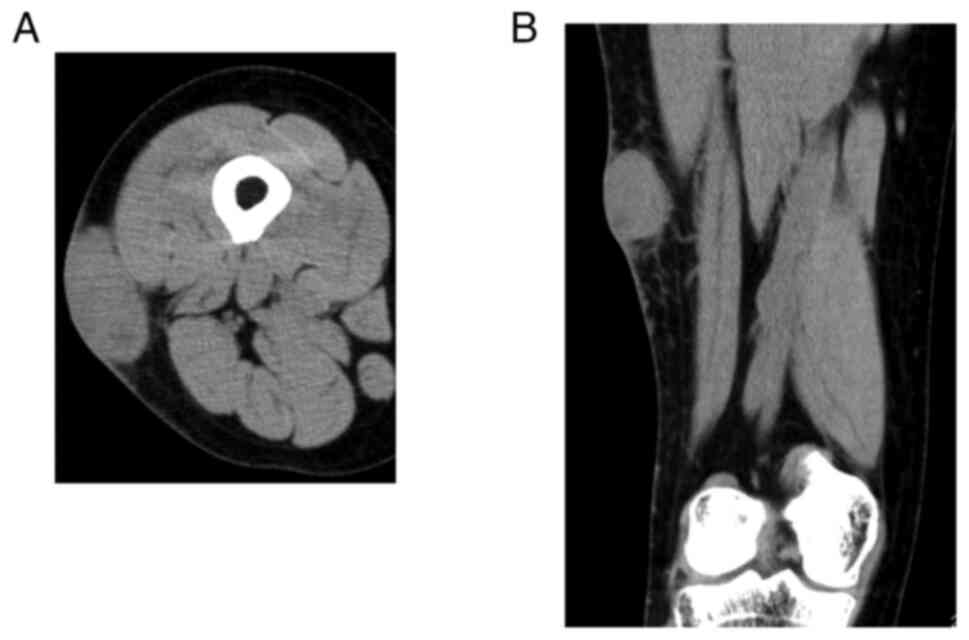

A 59-year-old woman visited Mie University hospital on January, 2013 due to a painless mass on her right thigh. After a needle biopsy was performed and she was diagnosed with LMS, she was subsequently referred to Mie University hospital. A physical examination and computed tomography (CT) confirmed a mass with a diameter of 5 cm on the postero-lateral side of the right thigh (Fig. 1). CT of the chest, abdomen and pelvis did not demonstrate any distant metastases. Wide resection of the tumor was performed. Tissue was fixed in 10% neutral-buffered formalin, embedded in paraffin. Tissue sections were sliced at 4 µm thickness, and stained with hematoxylin and eosin. Histological analysis using light microscope showed the proliferation of spindle cells with pleomorphic nuclei. The cells were set in long intersecting fascicles parallel and perpendicular to the plane of the section. Immunohistochemically, the tumor was positive for α-smooth muscle actin, desmin, and HHF35, but negative for S100 (Table I), which was consistent with the findings of LMS (Figs. 2A and B, and 3). After 1 year, she developed lung and bone metastases. Therefore, systemic chemotherapy using doxorubicin and ifosfamide was administered. Radiofrequency ablation (RFA) was performed for multiple bilateral pulmonary metastases. The bone metastasis was located in the mid-shaft of the femur. Cryoablation, curettage, and fixation with plate and cementation were performed to prevent fracturing. A total of 3 years after the initial surgery, she developed a bone metastasis in the right sixth rib. A resection of the sixth rib combined with resection of the fifth and seventh rib, to acquire a wide surgical margin was performed. A total of 5 years after the surgery, the patient developed sacral and skull bone metastases; thus, 11 cycles of trabectedin plus radiotherapy was prescribed. RFA was performed for residual multiple bilateral pulmonary metastases. After 6 years, abdominal CT revealed pancreatic metastasis. Therefore, eribulin treatment was administered. After 9 years, the patient was admitted to the general hospital for melaena. A submucosal tumor with central erosion was identified in the stomach by endoscopy, and a biopsy was performed (Fig. 4). The histological findings were consistent with a diagnosis of LMS. On CT, the gastric metastatic tumor was not detected, and the size of the metastatic mass in the pancreas was found to be gradually increasing (Fig. 5). The resection ability of both pancreatic and gastric metastatic tumors was discussed with a multidisciplinary team, and laparoscopic distal pancreatectomy and splenectomy, with partial gastrectomy, were performed. Subsequent histopathological examination confirmed metastasis of the LMS (Fig. 2C). At the final follow-up, 6 months after the gastrectomy (10 years from initial treatment), systemic chemotherapy was administered for residual pulmonary nodules.

Figure 1

Computed tomography showing a 5 cm mass in the thigh (A) Axial view and (B) coronal view (Case 1).